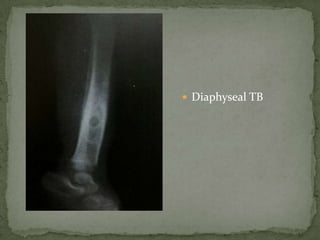

 Diaphyseal TB

Diaphyseal TB –

 Lytic lesion

 Marked periosteal

reaction

 Adjacent soft tissue

edema

 MRS – lactate peak